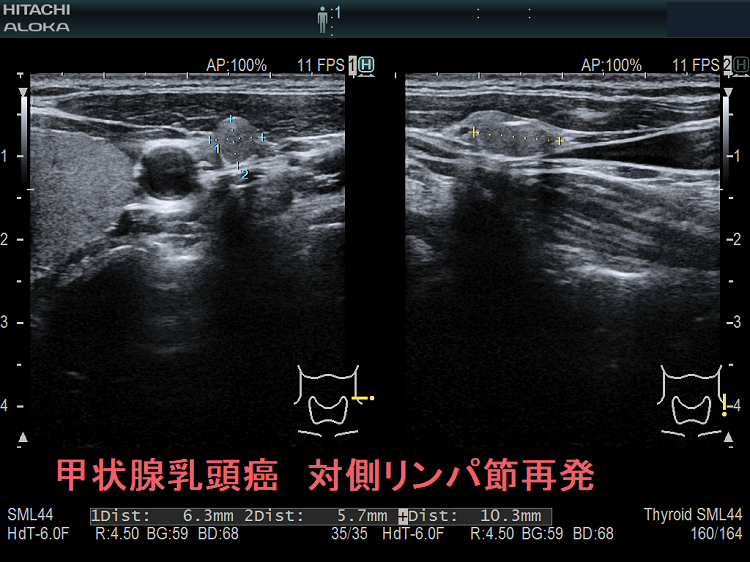

甲状腺乳頭癌の同側(切除した側)と対側(切除していない側)のリンパ節再発を同時に認めた症例

次の写真は甲状腺半葉切除(右葉)切除後リンパ節再発です。左右とも総頚動脈外側のリンパ節再発です。

甲状腺乳頭癌 対側(切除していない側)リンパ節再発 超音波(エコー)画像

甲状腺乳頭癌 対側(切除していない側)リンパ節再発 超音波(エコー)画像;等エコー、いびつな形で、周囲との境界が一部不明瞭化して浸潤を疑われる。リンパ門は消失。

甲状腺乳頭癌 対側(切除していない側)リンパ節再発 超音波(エコー)画像 ドプラーモード

甲状腺乳頭癌 対側(切除していない側)リンパ節再発 超音波(エコー)画像  ドプラーモード;内部に異常な走行の血管を認め、血流豊富。